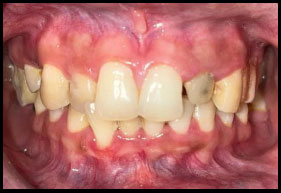

Peeso reamers (sizes 1 and 2) were used for post-space preparation, making sure that 3–4 mm of gutta-percha was retained at the apex. Next, a dual-cure resin cement was used to lute a prefabricated fiber-reinforced post into the canal (Fig. 3). Once the fiber post was in position (Fig. 4). Composite resin was then used to build up the core (Fig. 5). Occlusal view of the core build-up is shown in Fig. (6). Finally, a highly translucent all-ceramic crown was placed, restoring the tooth’s function and aesthetics in alignment with the surrounding dentition in occlusion (Fig. 7) and Occlusal view (Fig. 8).

Post operative.